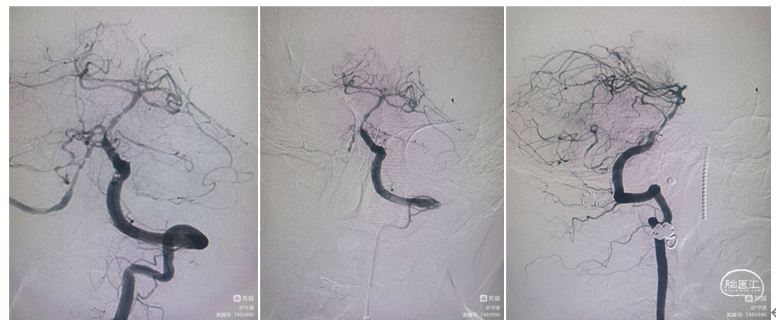

治疗过程

1、术中停用正在静脉泵入的替罗非班,予静脉肝素化(60u/kg, iv),肝素生理盐水稀释液持续冲洗导引导管。

2、0.035in导丝引导导引导管置于左侧椎动脉V2末端。

3、0.014in Synchro-2 soft 微导丝引导Echelon-10微导管置于左侧大脑后动脉P3段。

4、更换0.014in Floppy 300交换导丝,撤出微导管。

5、交换2.5*15mm球囊扩张导管,将球囊置于基底动脉狭窄处,缓慢充盈球囊至10ATM。

6、球囊完全泄压后回收,冒烟显示管腔狭窄解除。

支架植入:

1、选用Prowler Plus灌注微导管,沿交换导丝置于左侧P1段。

2、撤出微导丝,通过灌注微导管输送Enterprise-2支架,支架远端定位AICA(小脑下前动脉)开口近端,覆盖狭窄病变,释放支架后近端定位于左侧PICA开口远端(尽量不覆盖小脑后下动脉)。支架植入术后复查造影显示椎基底动脉狭窄解除。